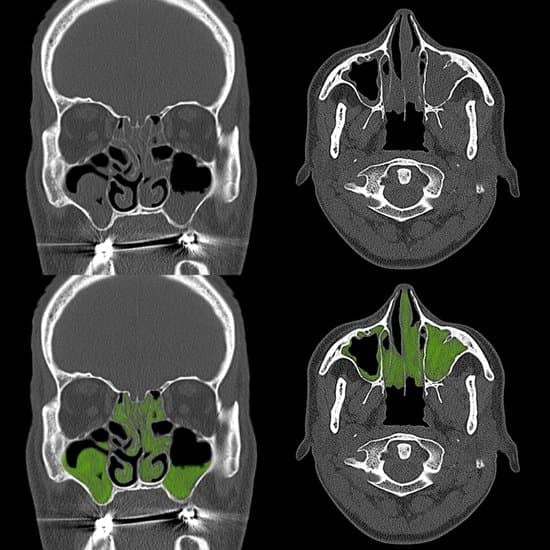

부비동염(또는 축농증)은 부비동(코 주위의 공기 주머니)에 염증이 생기는 질환입니다.

비중격만곡증(코의 중간 벽이 휘어진 상태), 부비동의 폴립(용종) 등의 구조적 문제는 부비동염의 발병 위험을 높입니다. 이러한 구조적 문제로 인해 부비동의 배출 통로가 좁아지거나 막히게 되면 염증이 쉽게 발생할 수 있습니다.

구조적 문제로 인한 부비동염의 경우 수술이 필요할 수 있습니다. 예를 들어, 비중격만곡증 교정이나 부비동 내시경 수술을 통해 부비동의 통로를 넓히고 염증을 제거할 수 있습니다. 수술은 일반적으로 다른 치료법으로 증상이 개선되지 않을 때 고려됩니다.